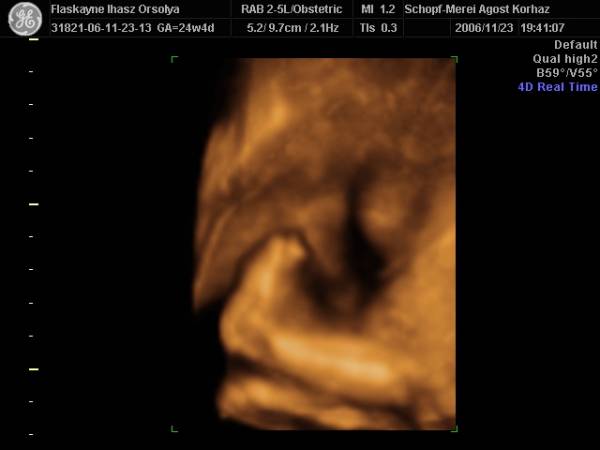

És aznap délután 4D!!!